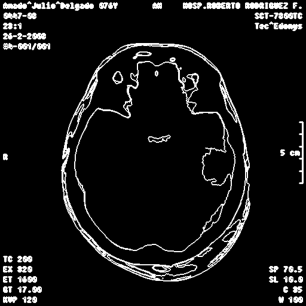

An example of an applications of our proposed strategy to a medical image is shown in Figure 7. In this case, we used different values of and in the . This is a preliminary result. A deeper paper about these results will be published.